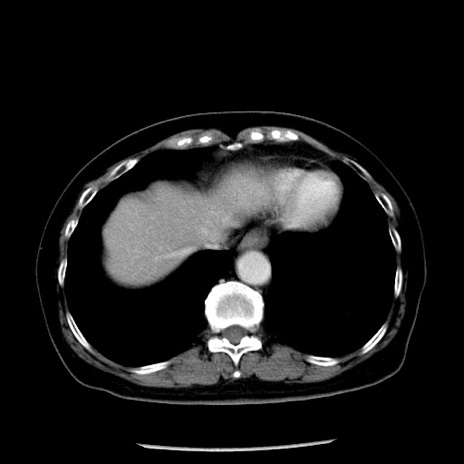

症例13(横断像)

冠状断像

【症例】70歳代女性

【主訴】腹痛、嘔吐

【現病歴】15時間程前(昨晩)より腹痛あり。今朝になっても症状の改善なく、嘔吐あり。腹痛も増悪あり、救急外来受診。

【既往歴】子宮癌全摘術後

【身体所見】意識清明、BP 121/72mmHg、P 74bpm、SpO2 100%(RA)、腹部:平坦・軟、腸雑音ほぼ聴取せず。下腹部・心窩部・臍左上に圧痛あり。反跳痛なし。

【データ】WBC 10600、CRP 0.15